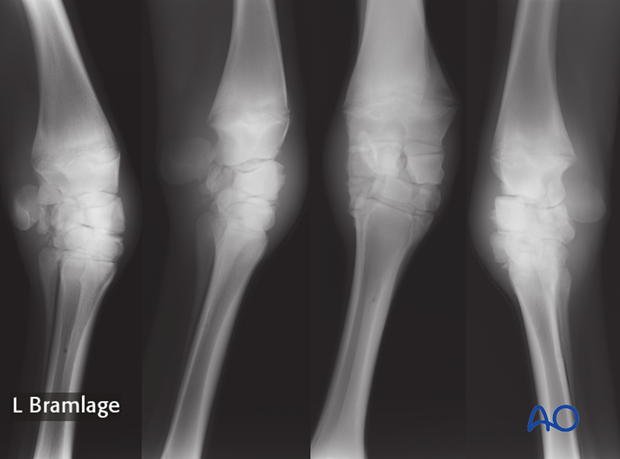

Fracture of the proximal row of the carpus.

Dorsopalmar, lateromedial and 45 degree oblique radiographs are necessary. Additional views may be indicated in certain cases.